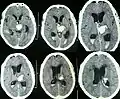

Le diagnostic de l'AAC se fonde sur les critères de Boston de 1995[14] modifiés en 2010[15]. Ces critères permettent de classer les patients en fonction du degré de probabilité du diagnostic. Le diagnostic de certitude est uniquement autoptique. Il est néanmoins possible de poser le diagnostic d'AAC possible ou probable du vivant du patient en s'appuyant sur un faisceau d'arguments essentiellement fondé sur les marqueurs hémorragiques à l'IRM cérébrale qu'il s'agisse de lésion en faveur d'une macrohémorragie cérébrale (> 1 cm de diamètre) ou de microhémorragie (diamètre < 1 cm).

Afin d'augmenter la sensibilité des critères de Boston, plusieurs marqueurs d'intérêts ont été évalués: des marqueurs d'imagerie en IRM et en TEP (tomographie par émission de positons) mais également biologiques à travers les marqueurs de protéines amyloïdes dans le liquide cérébrospinal (LCS).

- Marqueurs en IRM cérébrale. Outre les marqueurs hémorragiques déjà mentionnés, la valeur diagnostique de quasi tous les marqueurs classiques de microangiopathie à l'IRM ont été étudiés, en particulier pour différencier l'AAC de l'angiopathie hypertensive. En particulier, plusieurs travaux se sont intéressés à la distribution des hypersignaux de la substance blanche. L'AAC semble se caractériser par une tendance à présenter des hypersignaux de substance blanche plutôt cortico-sous-corticale (proche du cortex) alors que l'angiopathie hypertensive touche plus spécifiquement les capsules externes et le tronc cérébral[18]. La présence d'hypersignaux punctiformes en IRM de diffusion a également été considéré comme un marqueur potentiel de l'AAC, mais cette association n'a pas été retrouvée dans une méta-analyse de 2018[19]. À l'heure actuelle, seule la présence de dilatation des espaces de Virchow-Robin de topographie sous-corticale a montré une bonne corrélation avec les données histologiques.